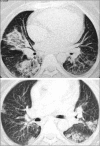

Bronchiolitis obliterans organizing pneumonia (BOOP) was first described in the early 1980s as a clinicopathologic syndrome characterized symptomatically by subacute or chronic respiratory illness and histopathologically by the presence of granulation tissue in the bronchiolar lumen, alveolar ducts and some alveoli, associated with a variable degree of interstitial and airspace infiltration by mononuclear cells and foamy macrophages. Persons of all ages can be affected. Dry cough and shortness of breath of 2 weeks to 2 months in duration usually characterizes BOOP. Symptoms persist despite antibiotic therapy. On imaging, air space consolidation can be indistinguishable from chronic eosinophilic pneumonia (CEP), interstitial pneumonitis (acute, nonspecific and usual interstitial pneumonitis, neoplasm, inflammation and infection). The definitive diagnosis is achieved by tissue biopsy. Patients with BOOP respond favorably to treatment with steroids.